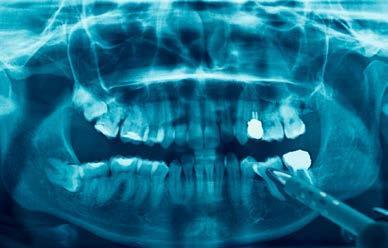

The panoramic radiograph (Figure 3) highlights the three missing premolars and absence of all third molars. Root length is excellent and periodontal support is good. The patient’s restorative index is low, a reflection of his history of regular dental care and good oral hygiene. The cephalometric radiograph, and analysis (Figure 4a and 4b) suggest a near-Class I skeletal relationship with mildly increased skeletal vertical dimension (MPA 35.8). Mandibular incisor angulation is significantly below average (IMPA 84.7), relative to the steeper than average mandibular plane. Visually, incisor angulation appears to be normal.

Figure 3: INITIAL panoramic radiograph Figures 4a and 4b: Initial cephalometric radiograph and analysis